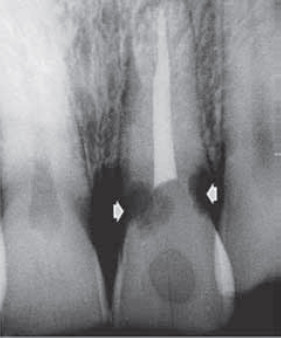

Jakie objawy mogą występować w sytuacji przedstawionej na poniższym zdjęciu rtg?